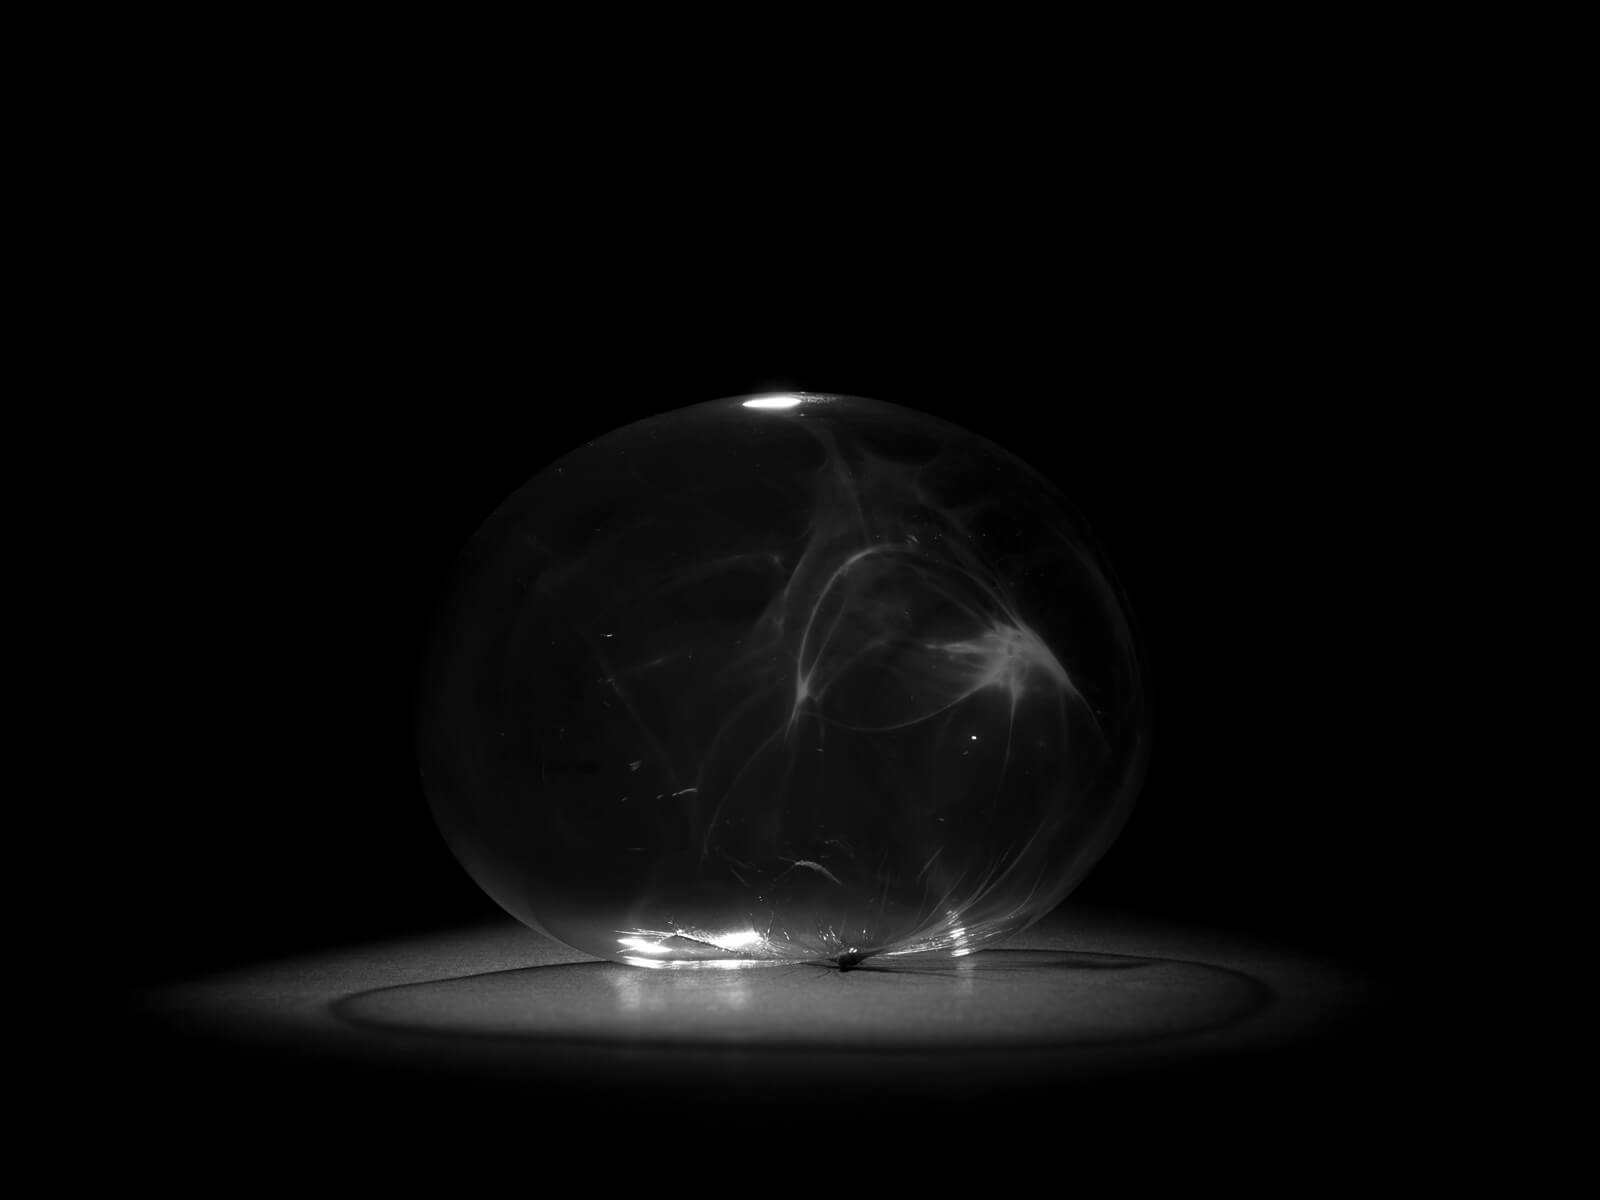

In queste immagini viene rappresentato, in chiave concettuale, il modo in cui la malattia agisce: i tessuti che si lacerano, il corpo umano che lentamente si spegne e infine l’intervento del farmaco, che ricostruisce ciò che è stato distrutto, generando una sorta di “bolla” protettiva attorno alle fragilità. L’intera scena si svolge in un limbo astratto, uno spazio vuoto e sospeso che priva l’ambiente di distrazioni, invitandoci a concentrare lo sguardo esclusivamente sugli oggetti e sulla dinamica che essi rappresentano. Accanto a questa narrazione visiva, con immagini di repertorio, emergono anche le motivazioni personali che hanno spinto la ricercatrice a intraprendere il proprio percorso. La perdita della madre, strappata via dalla sclerosi multipla, ha segnato profondamente il suo vissuto. La sua battaglia scientifica nasce da un forte bisogno di sconfiggere la malattia per impedire che altre persone subiscano lo stesso dolore. Il progetto si conclude con un ritratto della ricercatrice arricchito da sovrapposizioni fotografiche di persone a lei care, figure fondamentali che hanno contribuito a renderla la donna che è oggi. In questo ultimo scatto, emerge un’immagine luminosa e serena, una donna consapevole, grata per ciò che ha vissuto, per ciò che ha costruito e fiduciosa in ciò che potrà raggiungere.